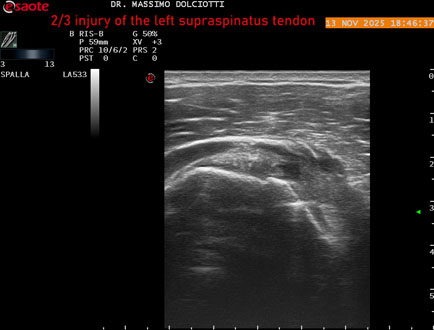

Data inserimento: 18/11/2025

Ecografia del: 13/11/2025

Strumento: Esaote MyLab Eight

Sonda: Lineare Multifrequenza 3-13 MHz

Età Paziente: M 58 anni

Motivazione dell'esame: da 4-5 mesi dolore alla spalla sinistra.

Commento all'esame: le immagini ed il video documentano il tendine sovraspinato sinistro disomogeneo per evidenza, in sede mediale sottobursale, di area ipoecogena di 4,5 mm per uno spessore di 3,3 mm, da ricondurre a lesione parziale che interessa i 2/3 del tendine.

Conclusioni: lesione 2/3 del tendine sovraspinato sinistro (2/3 injury of the left supraspinatus tendon).